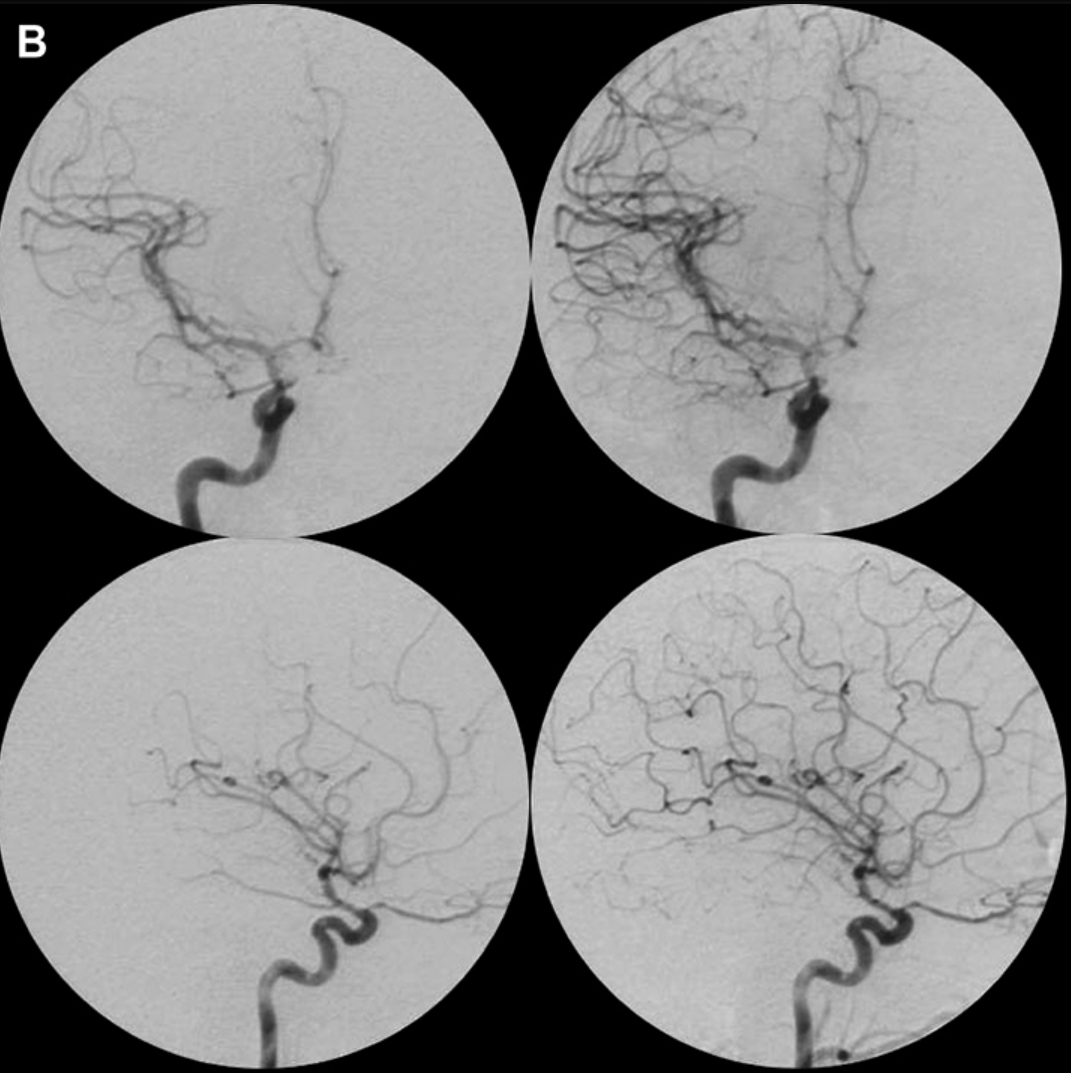

术后:同角度血管造影片,证实AVM被完全切除,无残留畸形团及动静脉分流现象。